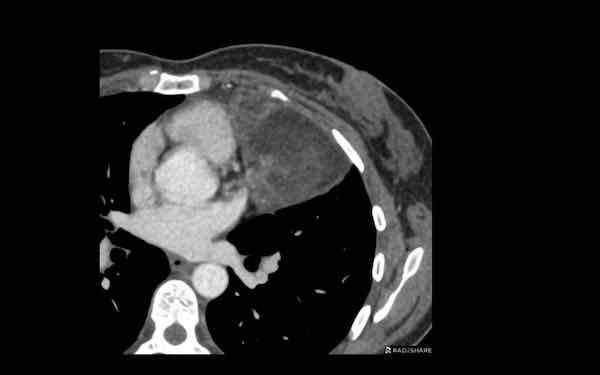

U lympho

Các hình ảnh này của một bệnh nhân nữ 60 tuổi.

Bệnh nhân có rối loạn nhịp tim và phát hiện tình cờ một khối trên CT ngực.

Hình ảnh

Khối có tỷ trọng cao trên phim chụp sau tiêm thuốc cản quang.

Không có mỡ đại thể.

Bờ hơi không đều.

Và có một khối thứ hai (mũi tên). Trên các lớp cắt khác còn thấy thêm nhiều khối nữa.

Thảo luận

Khi có nhiều khối, chẩn đoán có khả năng nhất là u lympho.

Bất cứ khi nào u lympho nằm trong chẩn đoán phân biệt, cần phải lấy mẫu mô và bắt đầu hóa trị ngay khi xác định được loại u lympho.